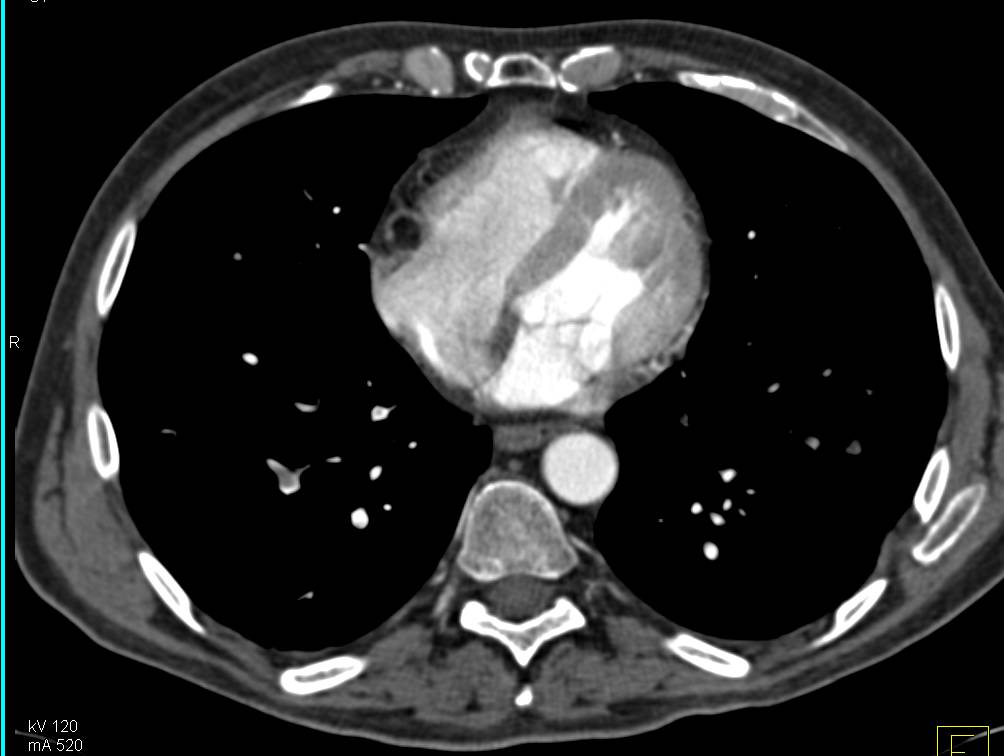

Aberrant Right Subclavian Artery in Patient with Dilated Ascending Aorta